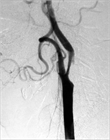

1. 典型症例として症候性内頚動脈狭窄について画像を用いて解説した。詳細は本文を参照されたい。